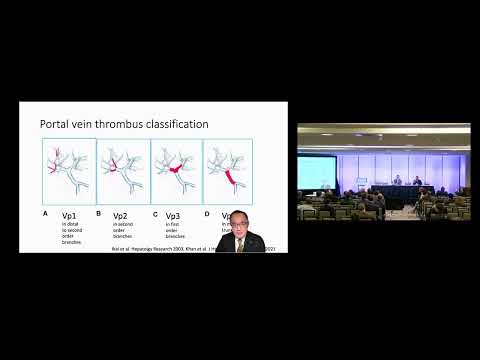

DEB09: HCC Macrovascular Invasion Resection

Debate 09: HCC Macrovascular Invasion Resection